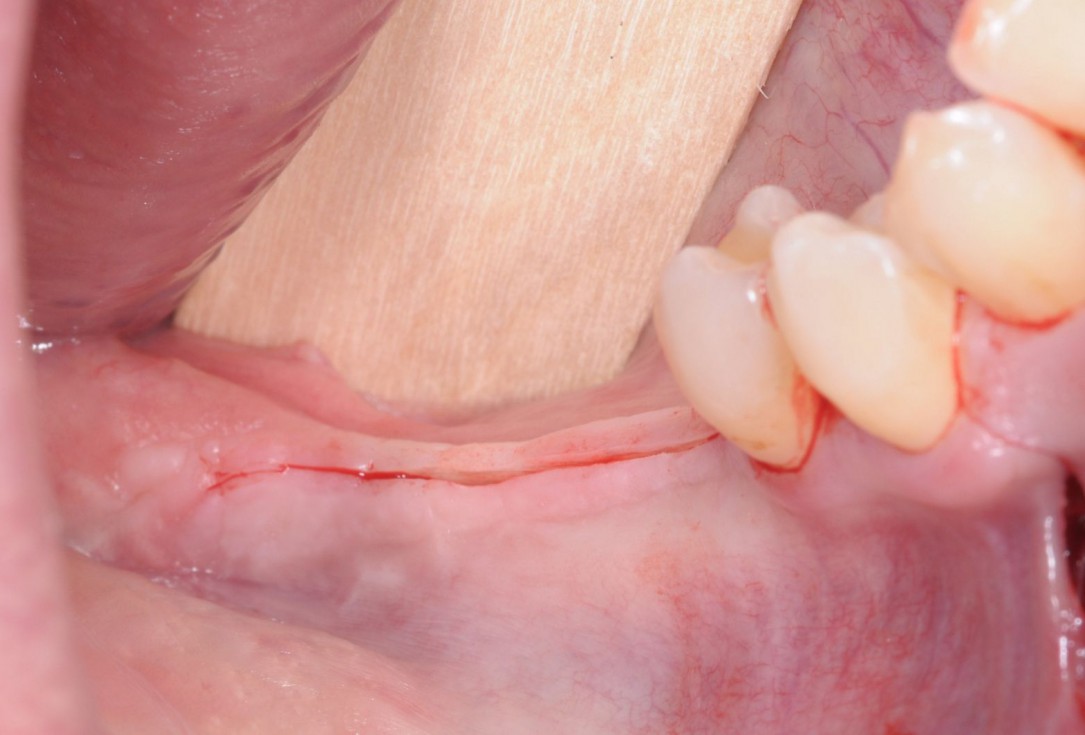

15/28 - Clinical situation 5 months after ridge augmentationThree-dimensional augmentation with maxgraft® cortico - Dr. R. Würdinger

16/28 - Surgical site opening along the initial incision lines to prevent further scar tissue formationThree-dimensional augmentation with maxgraft® cortico - Dr. R. Würdinger